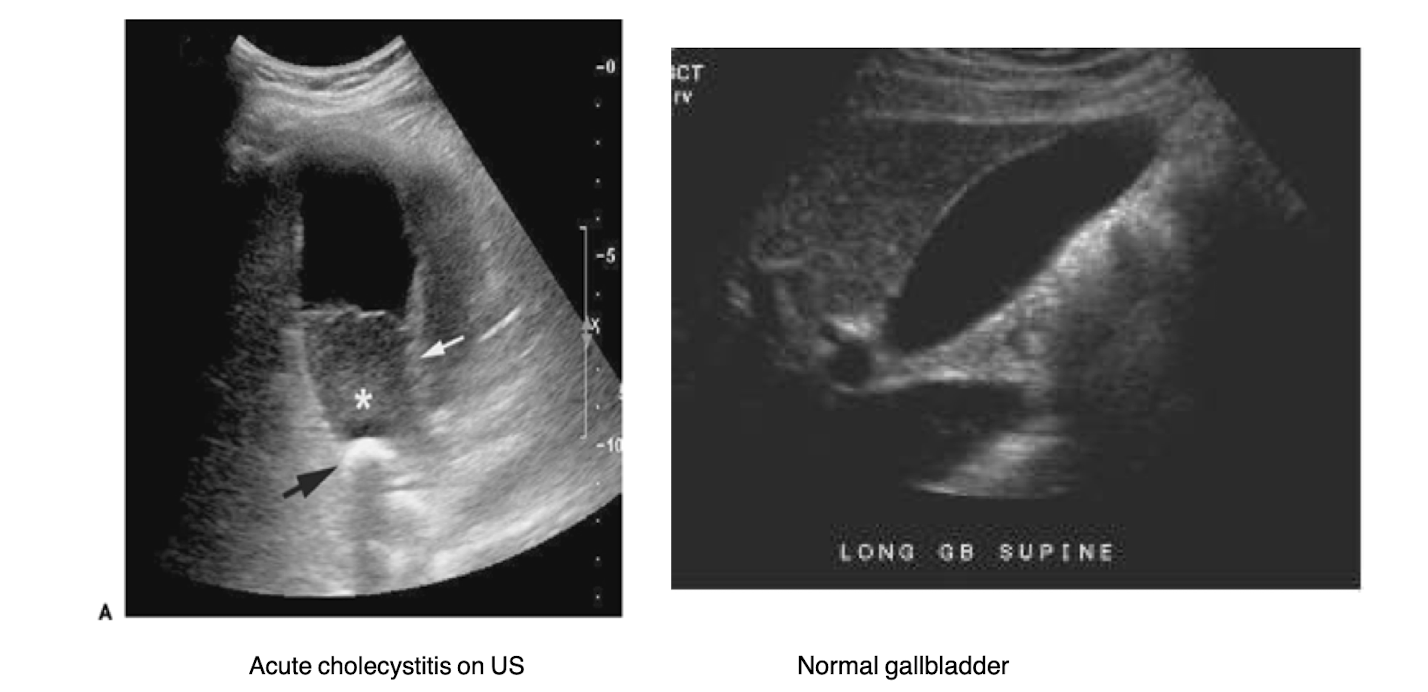

The left image is normal. What is occurring in the right image?

dilated common bile duct